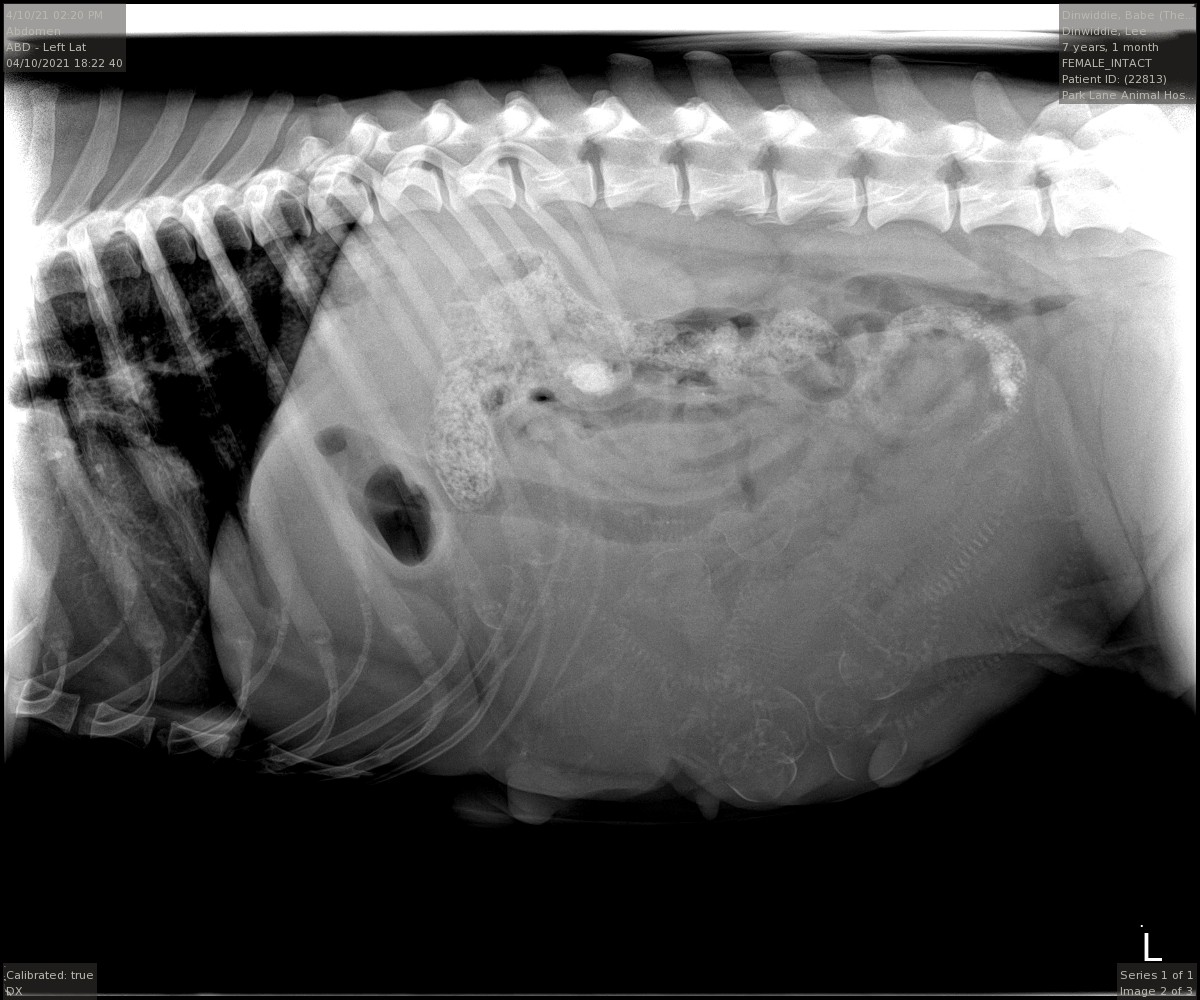

What is the pic?

Looks like a fish to me but I'm guessing a litter of very young puppies.0

Awe it's a puppy ultrasound

ABs Puppies!

I can never see what ultra sounds are supposed to show. I'll assume that all is well. Way to go, Babe.

Its actually a radiograph (x-ray). The trick is to count the skulls for the number of puppies. I count 9 skulls. That is day 48. Her last litter of 10 whelped at day 59, which could be April 21st this time if she conceived on the first breeding. Everything is well.1

- Anyone else but me see the fish? Don't tell Babe I said that.

Lee, I’m too excited. I knew exactly what I was looking at. Woo hoo. Puppies